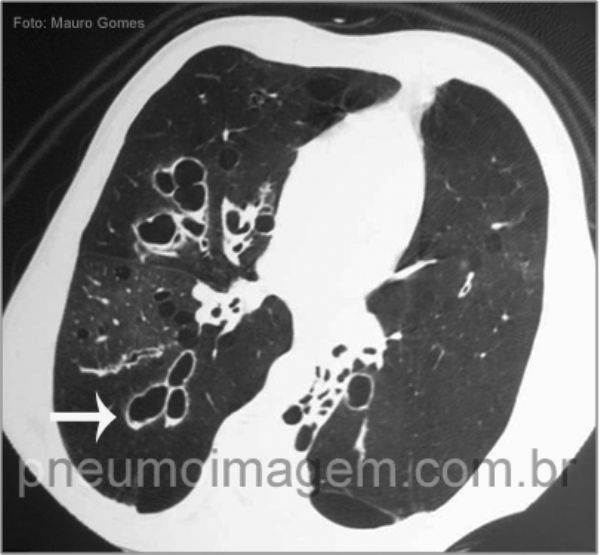

Neste corte tomográfico referente ao mesmo paciente da imagem anterior, observam-se extensas bronquiectasias centrais (seta branca) associadas ao padrão de perfusão em mosaico, que pode ser atribuído ao aprisionamento aéreo provocado pela doença.

Central bronchiectasis (white arrow) associated with the pattern of mosaic perfusion, which may be due to air trapping caused by the disease. The role of genetic deficiency of alpha-1 antitrypsin deficiency as a cause of bronchiectasis is not well established, but it is recommended its investigation in cases of bronchiectasis associated with emphysema in young adult.